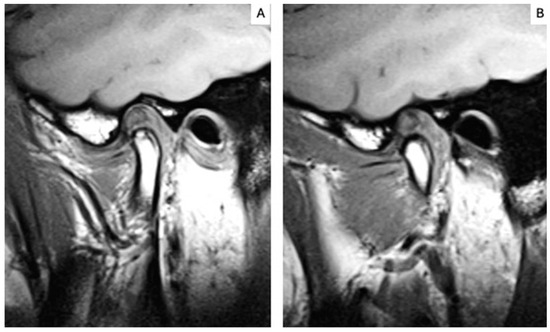

2.5. MRI Analysis